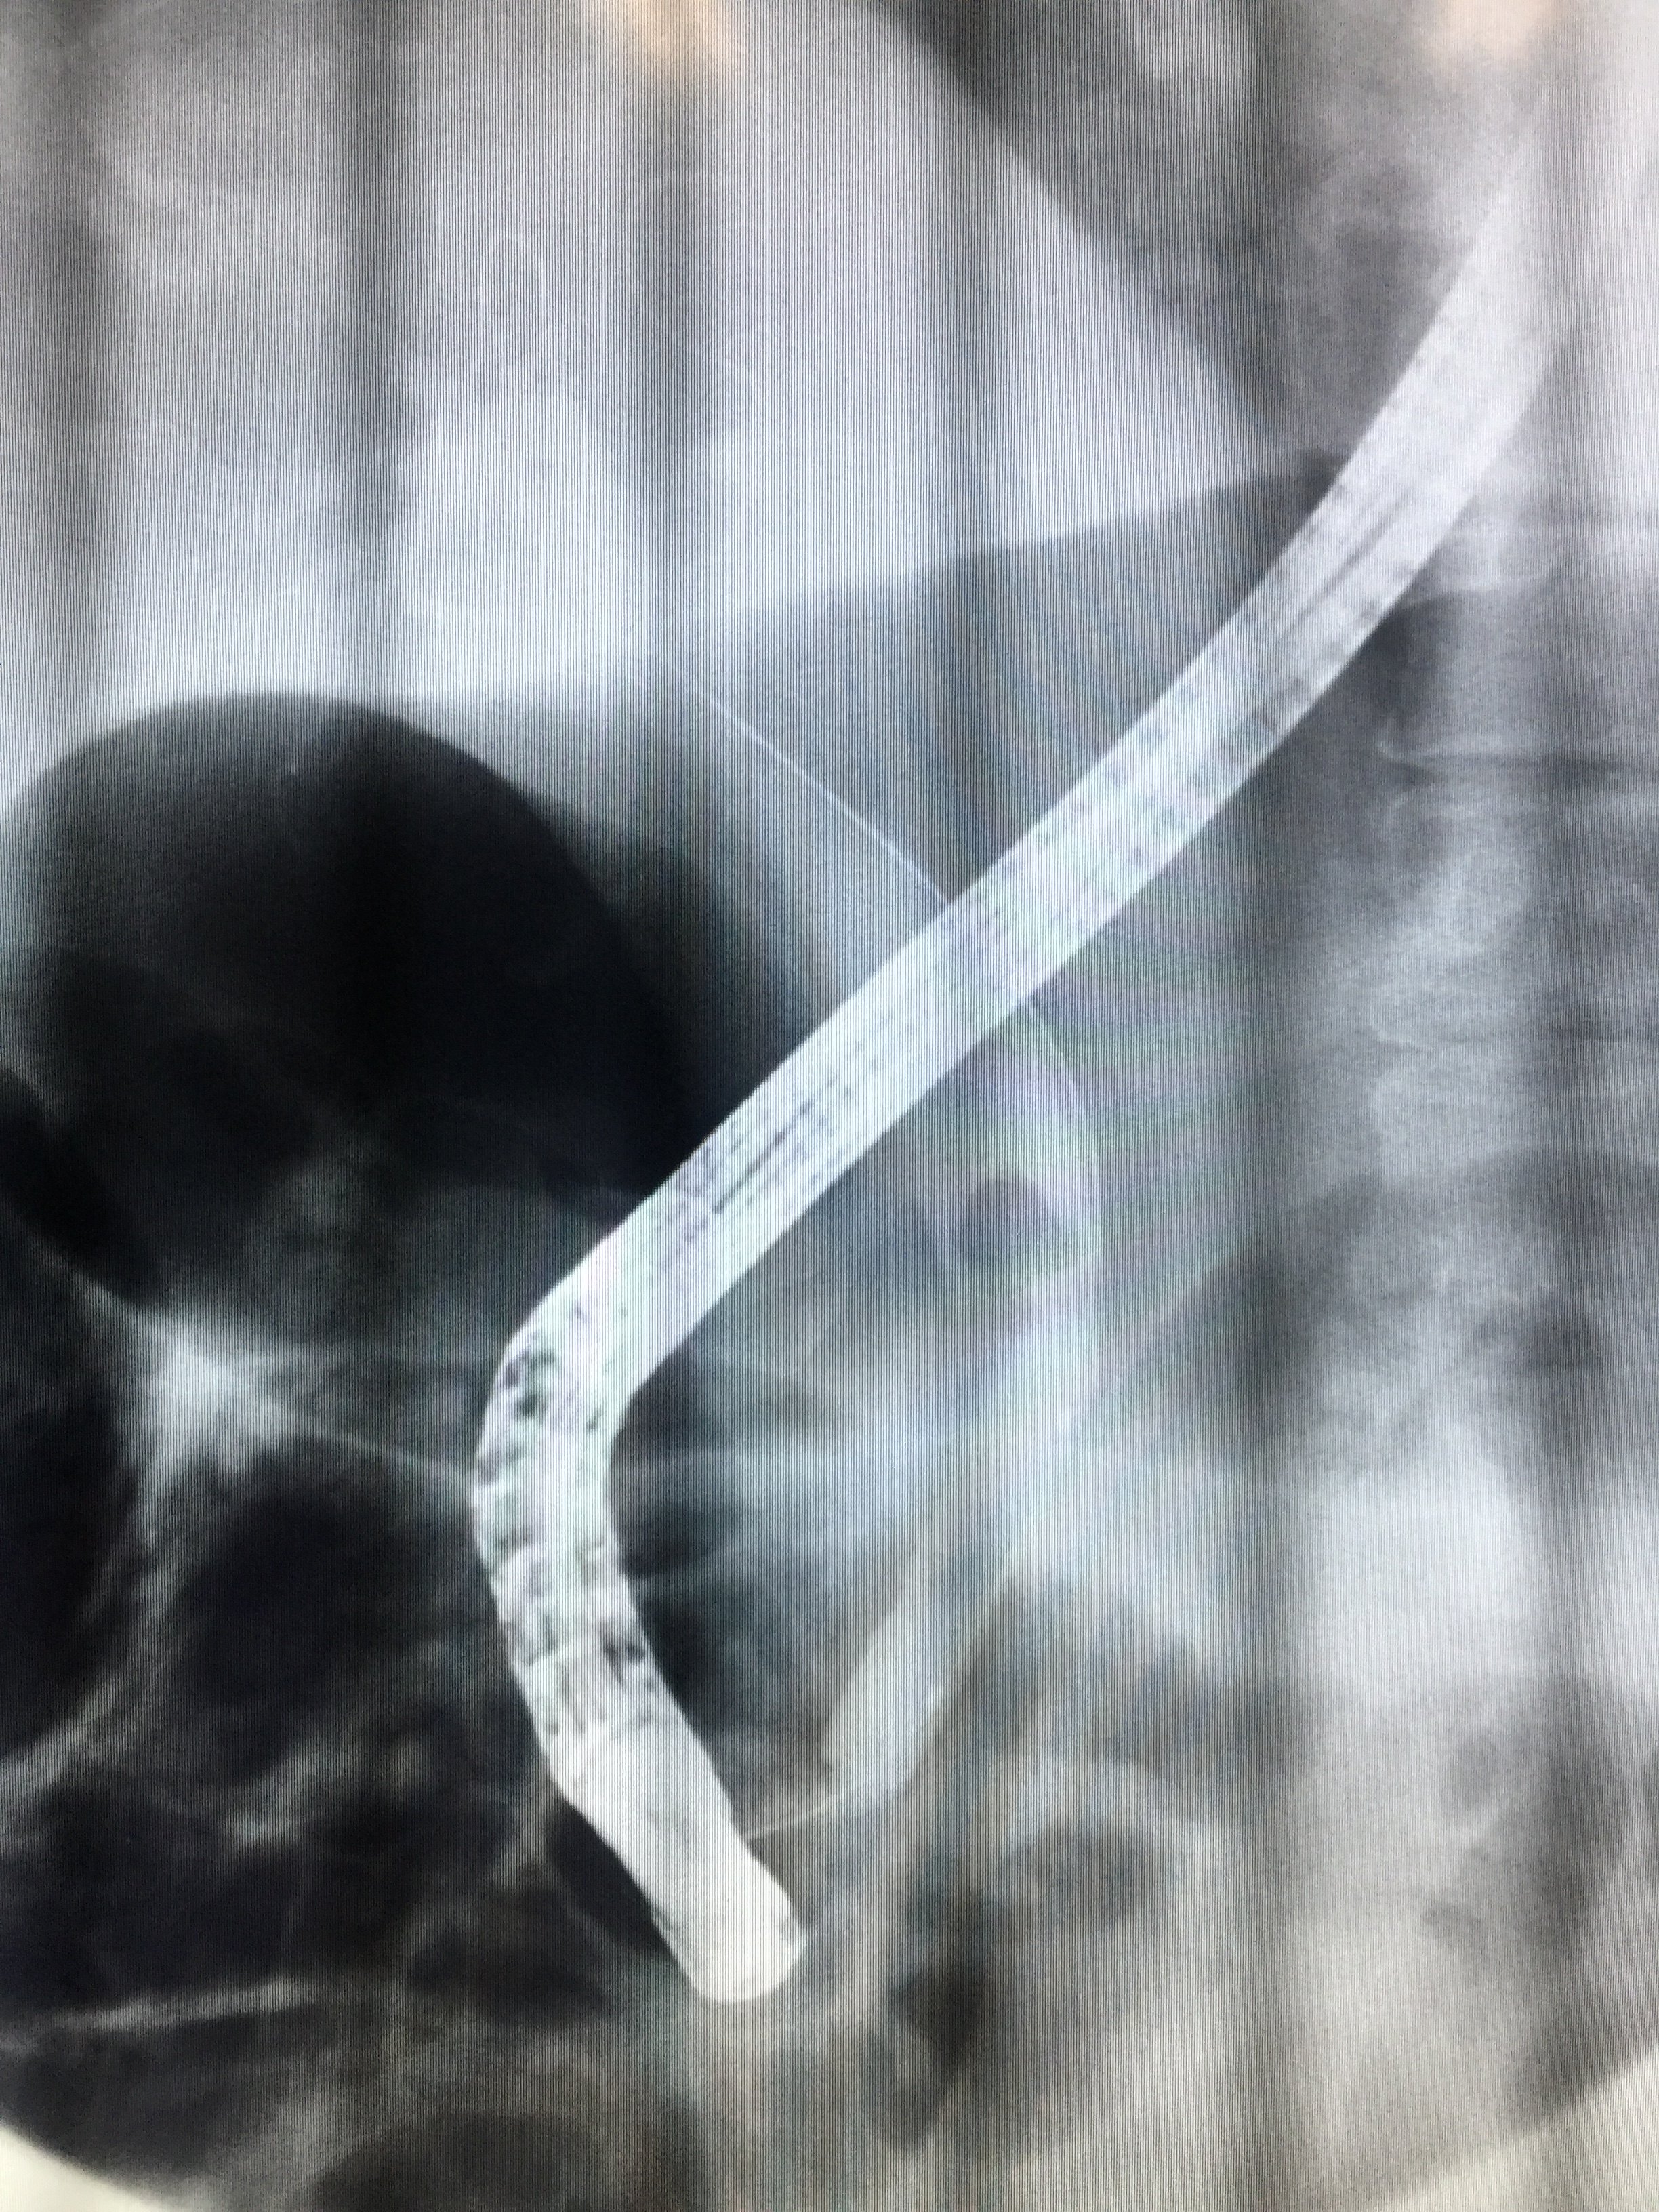

减黄1周后,造影,胆管扩张缓解,胆总管内巨大结石

胆总管结石术后,t管造型